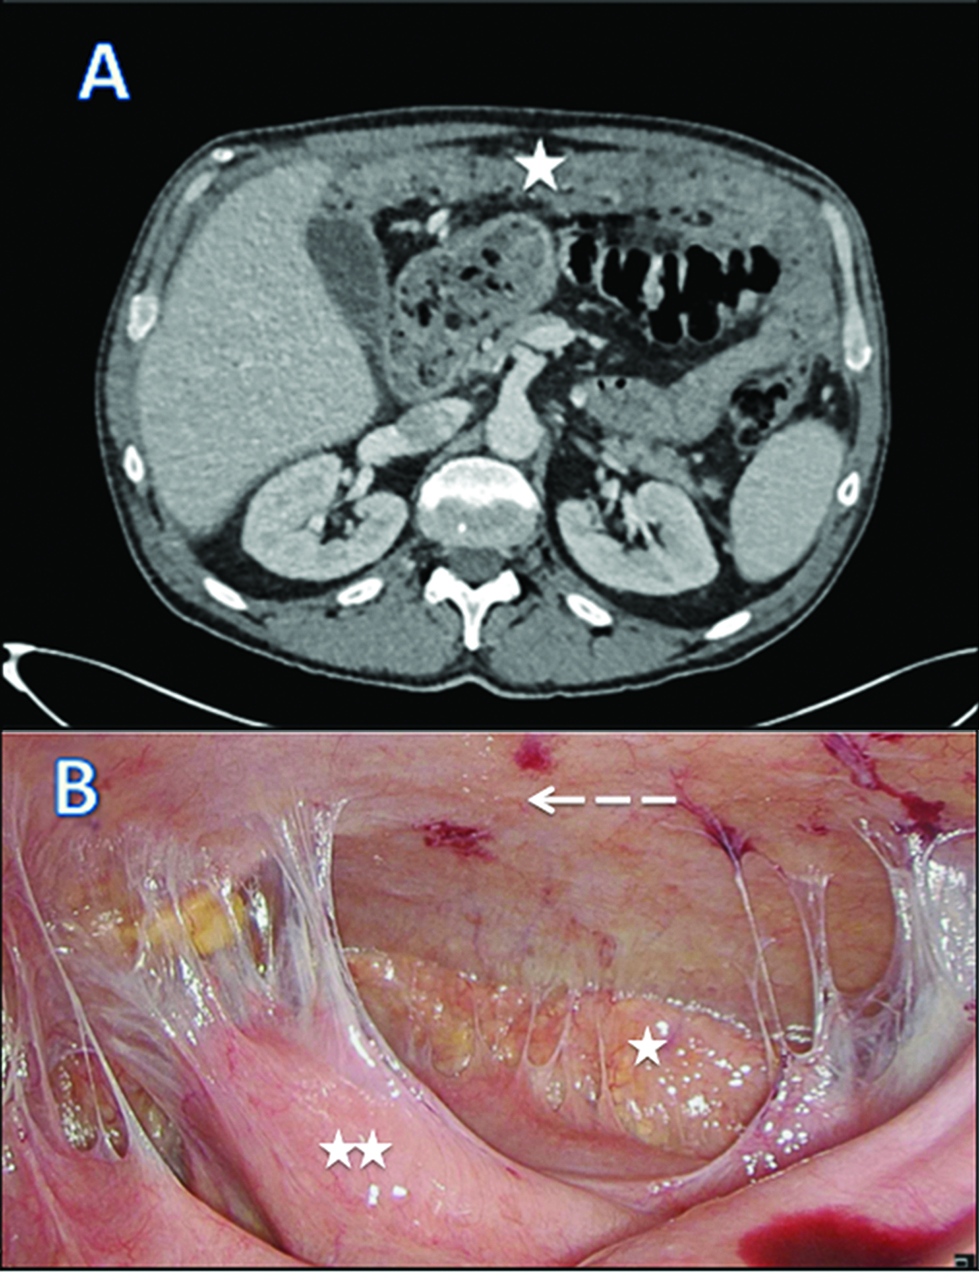

We report a case of 55-year-old male with the diagnosis of malignant peritoneal mesothelioma (MPM). Initial evaluation with CT-scan and laparoscopy reveals unresectable peritoneal carcinomatosis with PCI at 39 with thickened omentum (star), small bowel (2 stars) and parietal peritoneum (dash-arrow) deposit, ascitis (plane-arrow) (Figure 1A, B). Bidirectional chemotherapy (BDC) has been performed after three cycles of intravenous (IV) CISPLATIN – PEMETREXED, with intensification combining three cycles of IV PEMETREXED with intraperitoneal (IP) CISPLATIN (Figure 2). At reevaluation, PCI was still at 39 with a macroscopic response (Figure 3A, B). The peritoneal disease was thinner allowing a complete CRS with DOXORUBICIN/CISPLATIN based-HIPEC.

CT scan (A) and laparoscopic evaluation (B) after bi–directional chemotherapy.